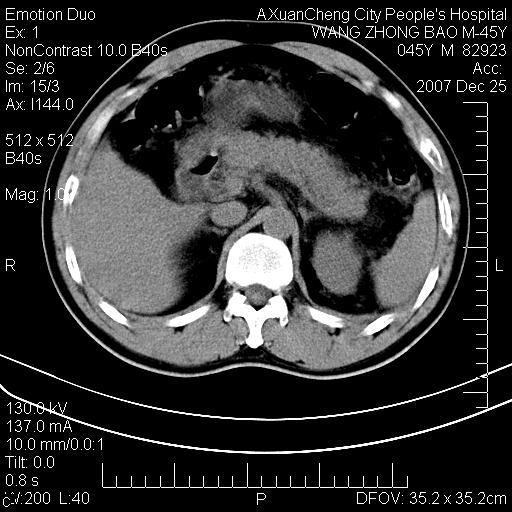

以下是引用qiuleiyu在2007-12-25 18:14:00的发言:[br]胰腺增大,周边渗出改变,肾前筋膜明显增厚,示少量积液.胆囊壁毛糙,周边少许渗出,胆总管壁厚,异常强化,然扩张不明显.结合病程急短;考虑;胆管炎,胆囊炎,胆源性胰腺炎可能大,请结合实验室检查及随访.

以下是引用lisihao在2007-12-25 14:23:00的发言:[br]急性水肿型胰腺炎[br]依据:1、胰腺弥漫性肿大,边缘稍毛糙;[br] 2、双侧肾周筋膜增厚,尤以左侧为甚(重要征象)[br] 3、双侧后胸膜增厚(刺激性炎症);[br] 4、结合病史,查血尿淀粉酶应该可以确诊。